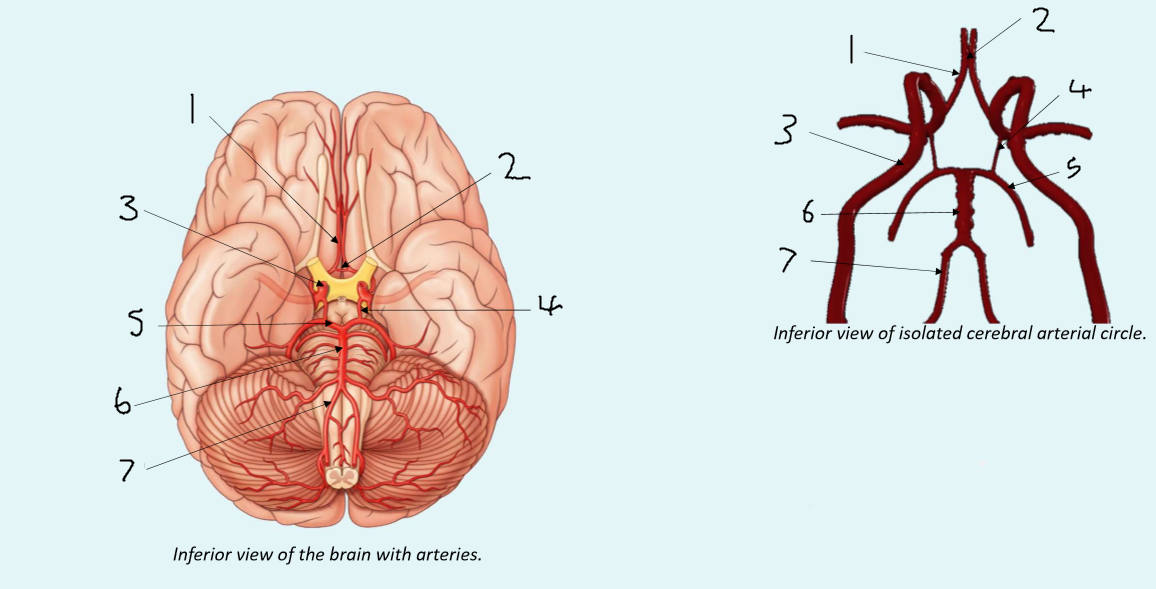

What is 1?

anterior cerebral artery

What is 2?

anterior communicating artery

What is 3?

internal carotid artery

What is 4?

posterior communicating artery

What is 5?

posterior cerebral artery

What is 6?

basilar artery

What is 7?

vertebral artery